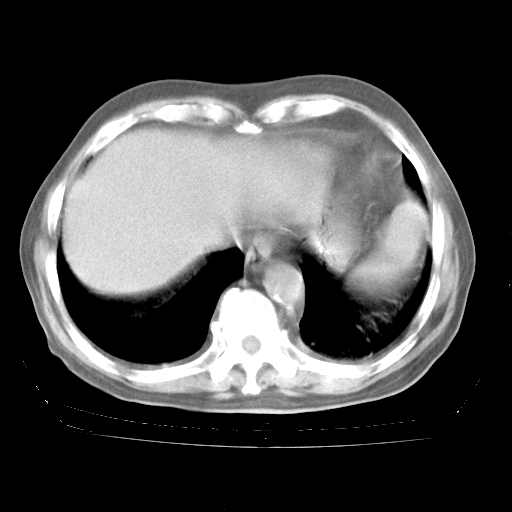

4月28日肺部CT

个人阅读4.14日肺部CT平扫:纵隔窗无异常,但肺窗示:双下肺内、后基底段有片絮状侵润影,部位以后基底段为著,以间质改变为主,呈急性肺泡炎征像,和首次住院影像学有相似之处。仅是个人读片,明日请相关专家再读片哈。其它建议同上。